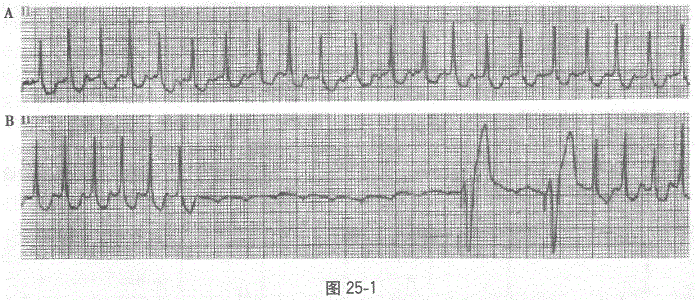

患者女,60岁,阵发性心悸5小时就诊,ECG如图25-1A,为窄QRS波群心动过速,心室率150次/分。图25-1B为心动过速发作时静脉推注三磷酸腺苷后心室停搏后紧急起搏心电图,其快速心律失常心电图诊断为

ECG诊断为:房性心动过速,VOO心室起搏,药物性房室传导阻滞。本图的心动过速为窄QRS波心动过速,频率为150次/分,故室上型心动过速的诊断可以确立。在QRS波之间难以分辨P波,似位于T波倒置的底部,即PR-RP,应考虑房室折返性心动过速、房扑(2:1下传)或房速。图B示静脉推注ATP后房室传导阻滞,给予心室保护性起搏。P波得以显露,心动过速没有终止,P波频率等于用药前心动过速的频率(150次/分)。从而除外房室折返性心动过速、房室结折返性心动过速及心房扑动,可以确定房速的诊断。ATP进入体内很快代谢为腺苷,因此其作用等同于腺苷的作用。腺苷直接作用于腺苷受体,也可兴奋迷走神经,具有抑制窦房结和房室结的自律性、延长不应期和抑制房室结传导的作用。在作用的部位上,对房室结和窦房结作用较强,对心房肌作用较弱,对心室肌作用最弱。通过本例也可以看出,腺苷对房室结作用最强,产生完全性的房室传导阻滞,但没有终止房速。因此腺苷可用于终止房室结、窦房结参与的心动过速,特别是房室折返性心动过速和房室结折返性心动过速,同时也可用于这些心动过速与心房扑动和大多数房速的鉴别诊断。